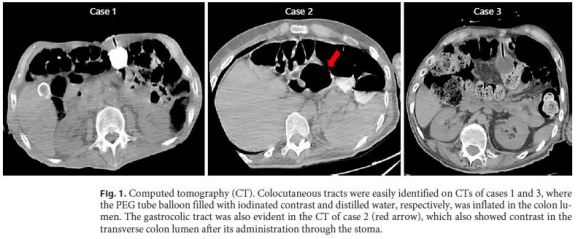

An 88-year-old man was referred to the artificial nutrition outpatient clinic in March 2007 for PEG. The patient was bedridden due to severe dyskinesia caused by Parkinson disease and was further diagnosed with an advanced larynx neoplasia causing airway obstruction and dysphagia, being not suitable for surgical resection. A tracheostomy was performed before PEG. The gastrostomy procedure was uneventful, and ambulatory enteral nutrition was maintained for several weeks. The patient remained asymptomatic and improved nutritional status during PEG feeding. Six months later, tube replacement was scheduled due to tube deterioration. In upper gastrointestinal endoscopy, the internal bumper was correctly positioned in the gastric body. It was looped using a polypectomy snare and removed by mouth according to the standard protocol of our center for replacing the initial PEG tube. A replacement tube with a distal inflation balloon was easily introduced through the stoma without resistance. No endoscopic control of the replacing tube was performed. One day later, the patient was admitted due to extravasation of fecaloid content through the tube. Abdominal computed tomography (CT) showed the PEG tube located in the colon and an iatrogenic colocutaneous fistula (Fig. 1). During hospital admission, parenteral nutrition was performed and stool drainage through the skin spontaneously resolved. Since there was no intraperitoneal leakage and the gastrocolic tract was not identified in the control CT, the patient was discharged under nasogastric feeding. A few weeks later, the skin orifice had completely closed without additional intervention. The risk of a new incidental colonic puncture caused by the complete colon interposition between the abdominal wall and the stomach led the team to avoid a new PEG. Given the patient’s anesthetic risk and his short life expectancy, a surgical gastrostomy was not performed. The patient remained using a long-term nasogastric tube until death, which occurred 1 month after hospital discharge.

A 31-year-old man with hereditary spastic paraplegia was referred to the artificial nutrition outpatient clinic in July 2017 due to prolonged dysphagia and need of a nasogastric tube for nutritional support. A PEG was scheduled for long-term enteral nutrition. During the procedure, abdominal transillumination was easily obtained and the PEG tube could be placed without immediate complications. The patient was followed in the ambulatory, remaining asymptomatic for several months. Seven months later, PEG tube deterioration was evident, and the replacement was planned. Endoscopy confirmed the intragastric position of the internal bumper, which was removed. Under endoscopic control, the replacement tube was easily inserted through the stoma; however, it did not reach the gastric lumen. Gastric cannulation was impossible even after using a rigid guidewire, and, therefore, the procedure was postponed and the patient admitted for investigation. CT showed complete interposition of the transverse colon between the stomach and the abdominal wall. After diluted loperamide contrast (Ultravist® 370, Bayer) administration through the stoma, colon opacification was observed without intraperitoneal extravasation. The gastrocolic tract was also identified (Fig. 1). The diagnosis of GCCF was confirmed. Since leakage through the skin was not observed as the orifice partially closed, the patient was immediately discharged under nasogastric feeding, being referred for surgical gastrostomy. After observing the patient and the CT images, the surgical team proposed a minimally invasive laparoscopic ap proach. The colocutaneous and gastrocolic tracts were easily identified and ligated using Hem-o-lok® (Fig. 2). The colocutaneous tract was resected and the cutaneous end excised from the outside. To ensure that the new gastrostomy was placed far from the gastric end of the gastrocolic tract, a percutaneous combined assisted laparoscopic and endoscopic gastrostomy was performed using the push method (Ballard introducer Kit Mic Key 20F) with gastropexy (Fig. 3). The patient was discharged after resuming enteral nutrition and maintained follow-up without additional complications.

A 45-year-old man with cerebral palsy was referred to the artificial nutrition outpatient clinic in January 2018 for PEG due to long-term dysphagia and nasogastric tube feeding. Although the patient presented a normal body mass index, abdominal transillumination was quite difficult to obtain, only being transiently observed below the xiphoid process. Gastric access was achieved, and the PEG tube could be placed after abdominal puncture, performed not completely perpendicular to the skin. Feeding tube transparietal thickness assessed at the end of the procedure was 5.5 cm. The patient remained asymptomatic under PEG feeding for several months. Seven months later, PEG tube replacement was proposed due to deterioration. Endoscopy showed the internal bumper in the stomach, which was removed. Under endoscopic control, the replacement tube inserted through the stoma did not reach the gastric lumen. Some stool vestiges could be observed in the tube at this time. CT showed the balloon inflated in the colon, even without contrast injection, and transverse colon interposition between the stomach and the abdominal wall (Fig. 1). The diagnosis of GCCF was assumed, and the patient was admitted to the gastroenterology ward for surveillance. After PEG tube removal, the skin orifice was partly closed avoiding stool drainage. The patient was further discharged under nasogastric feeding, being referred for surgical gastrostomy. A laparoscopic approach was selected by the surgical team. During the procedure, the colocutaneous and gastrocolic tracts were ligated and easily resected. Laparoscopic gastrostomy was performed using the push method with gastropexy. Gastrostomy feeding was resumed and nutritional follow-up maintained.